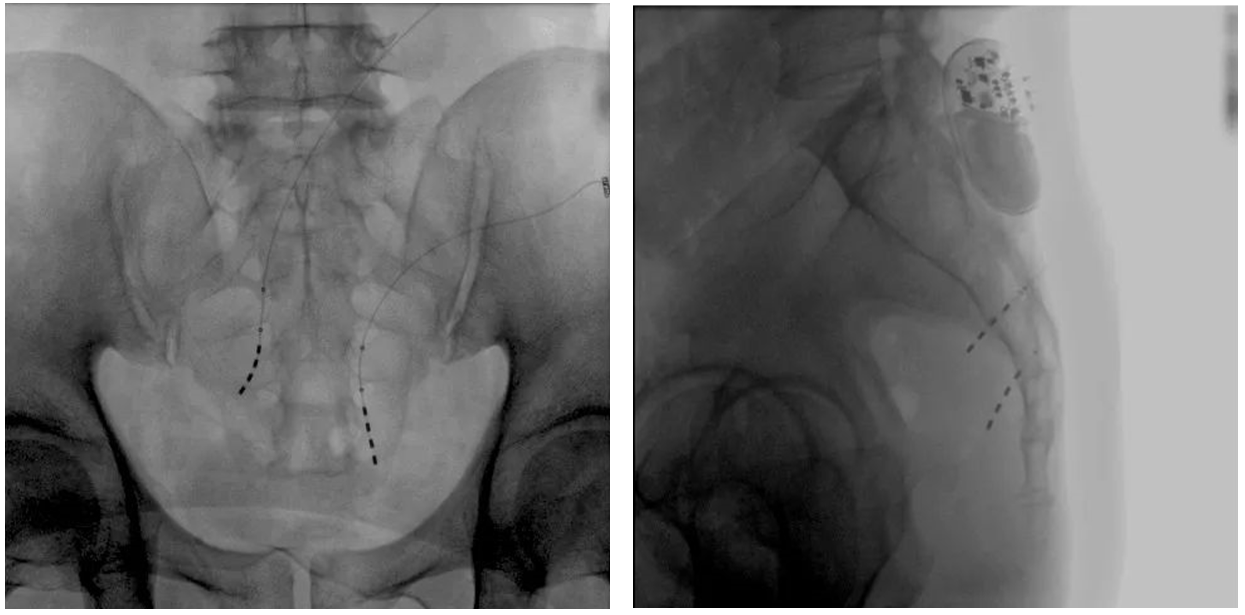

大平板一体式移动C形臂术中影像

在骶神经调控术或者骶神经刺激术(SNS)中,医师首先会在透视引导下把电极通过导针插入到骶3神经孔位置,通过脉冲电流的刺激,达到兴奋神经纤维并抑制逼尿肌收缩。在这一步,医师会先对患者的神经刺激反应做测试评估,如果刺激效果明显,说明该方案能够达到手术预期。接下来医师会在附近皮下脂肪处植入一块脉冲电流发生器并与电极相连,使该部位今后能得到长期的电刺激,改善OAB症状。

? 相较于影增C形臂,平板探测器成像的畸变更少,能够准确体现电极和骶孔位置关系,提高手术效果预期。